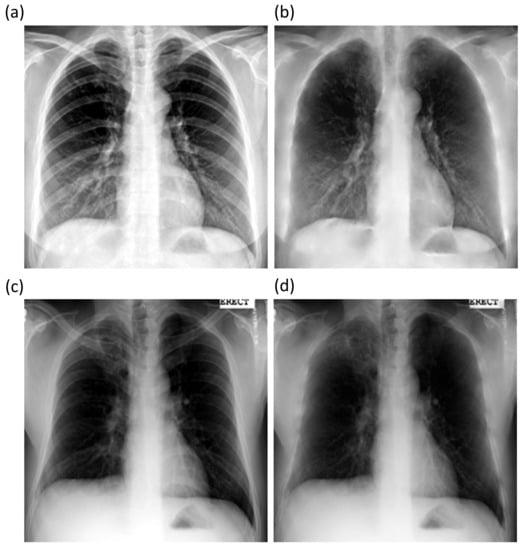

The best performing ResNet–BS model is further used to suppress bones in Shenzhen and Montgomery TB CXR collections. Figure 7 shows the bone-suppressed instances of a sample CXR from the Shenzhen and Montgomery CXR collections. It is observed that the ResNet–BS model generalized to the Shenzhen and Montgomery TB CXR collections that are not seen by the model during training or validation. The bone shadows are completely suppressed, and the resolution of the CXRs is preserved.

Figure 7. Bone-suppressed CXRs predicted by the ResNet–BS model using a sample CXR from the Shenzhen and Montgomery TB collection. (a) Shenzhen abnormal CXR; (b) Predicted bone-suppressed image; (c) Montgomery abnormal CXR; and (d) Predicted bone-suppressed image.